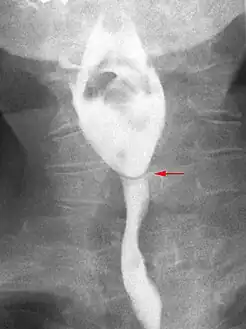

Esophageal webs are thin membranes occurring anywhere along the esophagus.[1]

Esophageal webs are thin 2–3 mm (0.08–0.12 in) membranes of normal esophageal tissue consisting of mucosa and submucosa that can partially protrude/obstruct the esophagus. They can be congenital or acquired. Congenital webs commonly appear in the middle and inferior third of the esophagus, and they are more likely to be circumferential with a central or eccentric orifice. Acquired webs are much more common than congenital webs and typically appear in the cervical area (postcricoid).

The diagnostic test of choice is a barium swallow.